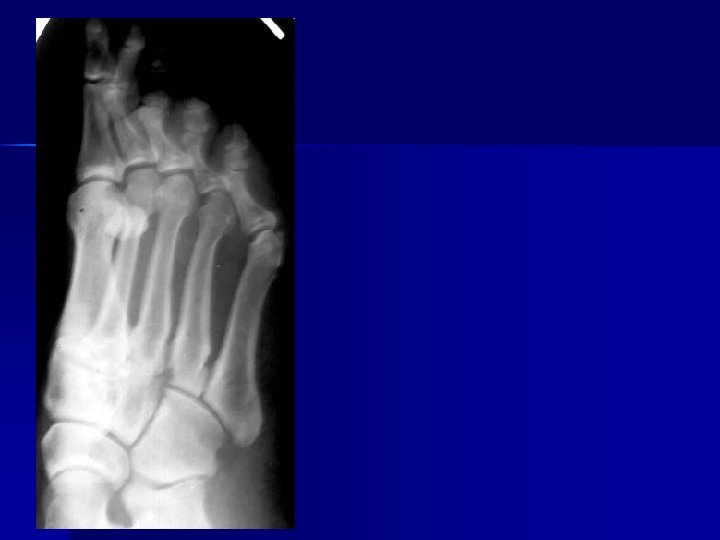

Name & cause of this?

Evaluating Images What do you think?

n n n Does this show good detail? Is all of the anatomy present? How is the density / contrast?